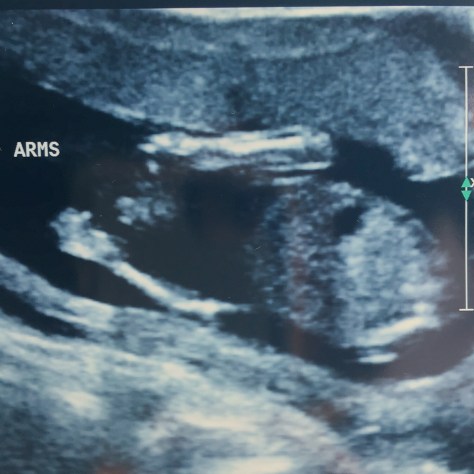

I will admit, I was not in a good state of mind entering another procedure room, having another large needle invade the safe little home that I have been slowly growing for our precious number 5. I have seen prayers go unanswered, I have witnessed loss when you least expect, but most of all the new OBGYN decided to freak me out by telling me a scary story of an amniocentesis ending badly…why on earth He would say it to a pregnant woman still baffles me. I had done the research before, understood the risks, but again was faced with this decision being made for me. High risk, history of genetic mutation are all on my medical chart. The unknown and Ezzys entrance into the world that required an airlift to Seattle and an entire team working to save her life now impacts her mom’s prenatal care she receives on a remote Alaskan island.

The amino went well, it was uncomfortable, but not like Ya’el’s and I left feeling completely covered and protected. How could I not, God had been busy that day, reminding me that he goes before me.